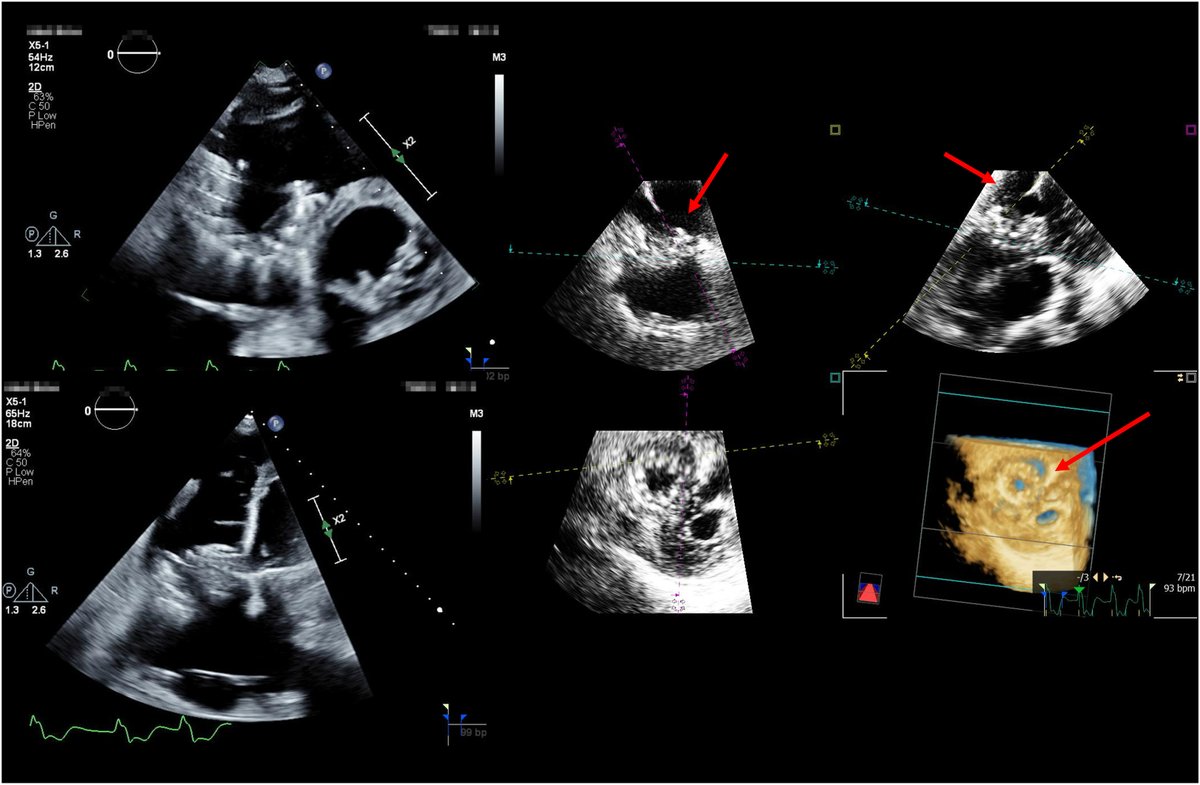

FANTASTIC MUST-READ #JACCIMG @JACCJournals SOTA review on Post #Evoque #TTVR Echo #TTE imaging. Comprehensive, practical! Download full paper here FREE for a LIMITED TIME! https://t.co/lfhJ0khJAw https://t.co/DgyCXnMOOF